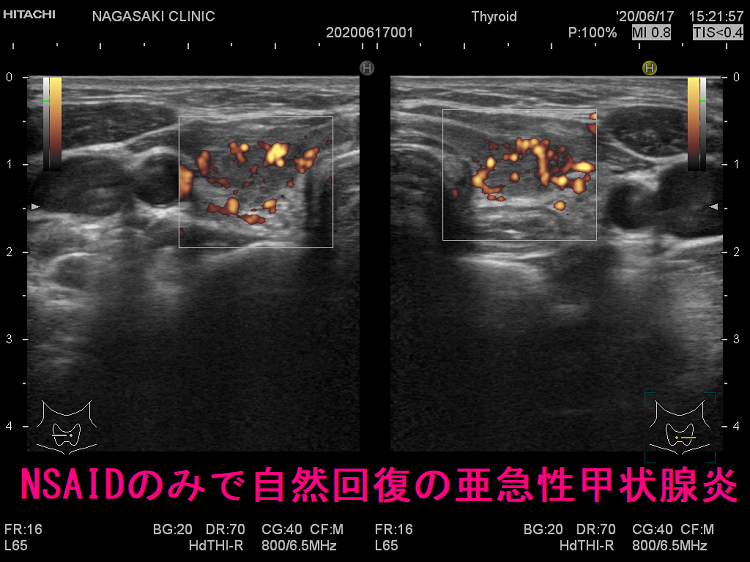

亜急性甲状腺炎の治療。副腎皮質ホルモン剤(ステロイド剤)が劇的に効き、2-3日で痛みは消え、熱も下がり治ったように錯覚。服薬中止で1週間以内に元に戻る。ステロイドを平均3-4か月掛けてゆっくり着実に減量。齲歯(虫歯)治療中、高齢者では使い難い。甲状腺機能亢進症/バセドウ病に使う抗甲状腺薬(メルカゾール、プロパジール、チウラジール)は無効。ロキソニンなどの非ステロイド系抗炎症剤(NSAIDs)は対症療法で、亜急性甲状腺炎自体の炎症を抑えない。ステロイドの副作用、高齢、齲歯(虫歯)治療中、自然治癒する可能性などの理由で使用。

ロキソニンなどの抗炎症薬(NSAIDs)は、痛みを和らげる・熱を下げる対症療法で、亜急性甲状腺炎自体の炎症を抑えません。抗炎症薬を使用するのは、

- 非常に軽度の亜急性甲状腺炎で、副腎皮質ホルモン剤(ステロイド剤)を投与しなくても自然治癒する可能性が高い